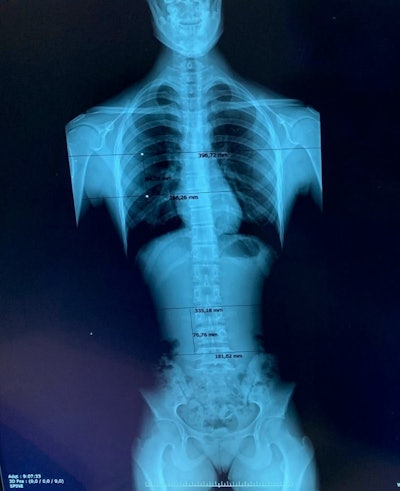

Estimated overlapping regions in the General Electric Definium 8000 unit for a patient with three projections.

Two systems are used to perform full spine studies at the Madrid hospital: a General Electric Definium 8000 machine and a Fuji FDR Smart Suspension system, which allows full-spine scans to be performed in one shot. For the latter, the detector consists of three regular detectors placed together, so there is no need to move the x-ray tube and detector down the spine, thus reducing artifacts and presumably patient effective doses due to non-overlapping.

In the study, 73 patients were imaged on the GE unit and 55 on the Fuji system. The entrance surface air kerma was calculated for each projection, from exposure and patient parameters manually recorded by the technologists during the studies. According to the images analyzed by the radiologists, a 6 cm region of overlap was considered between images for the conventional system.